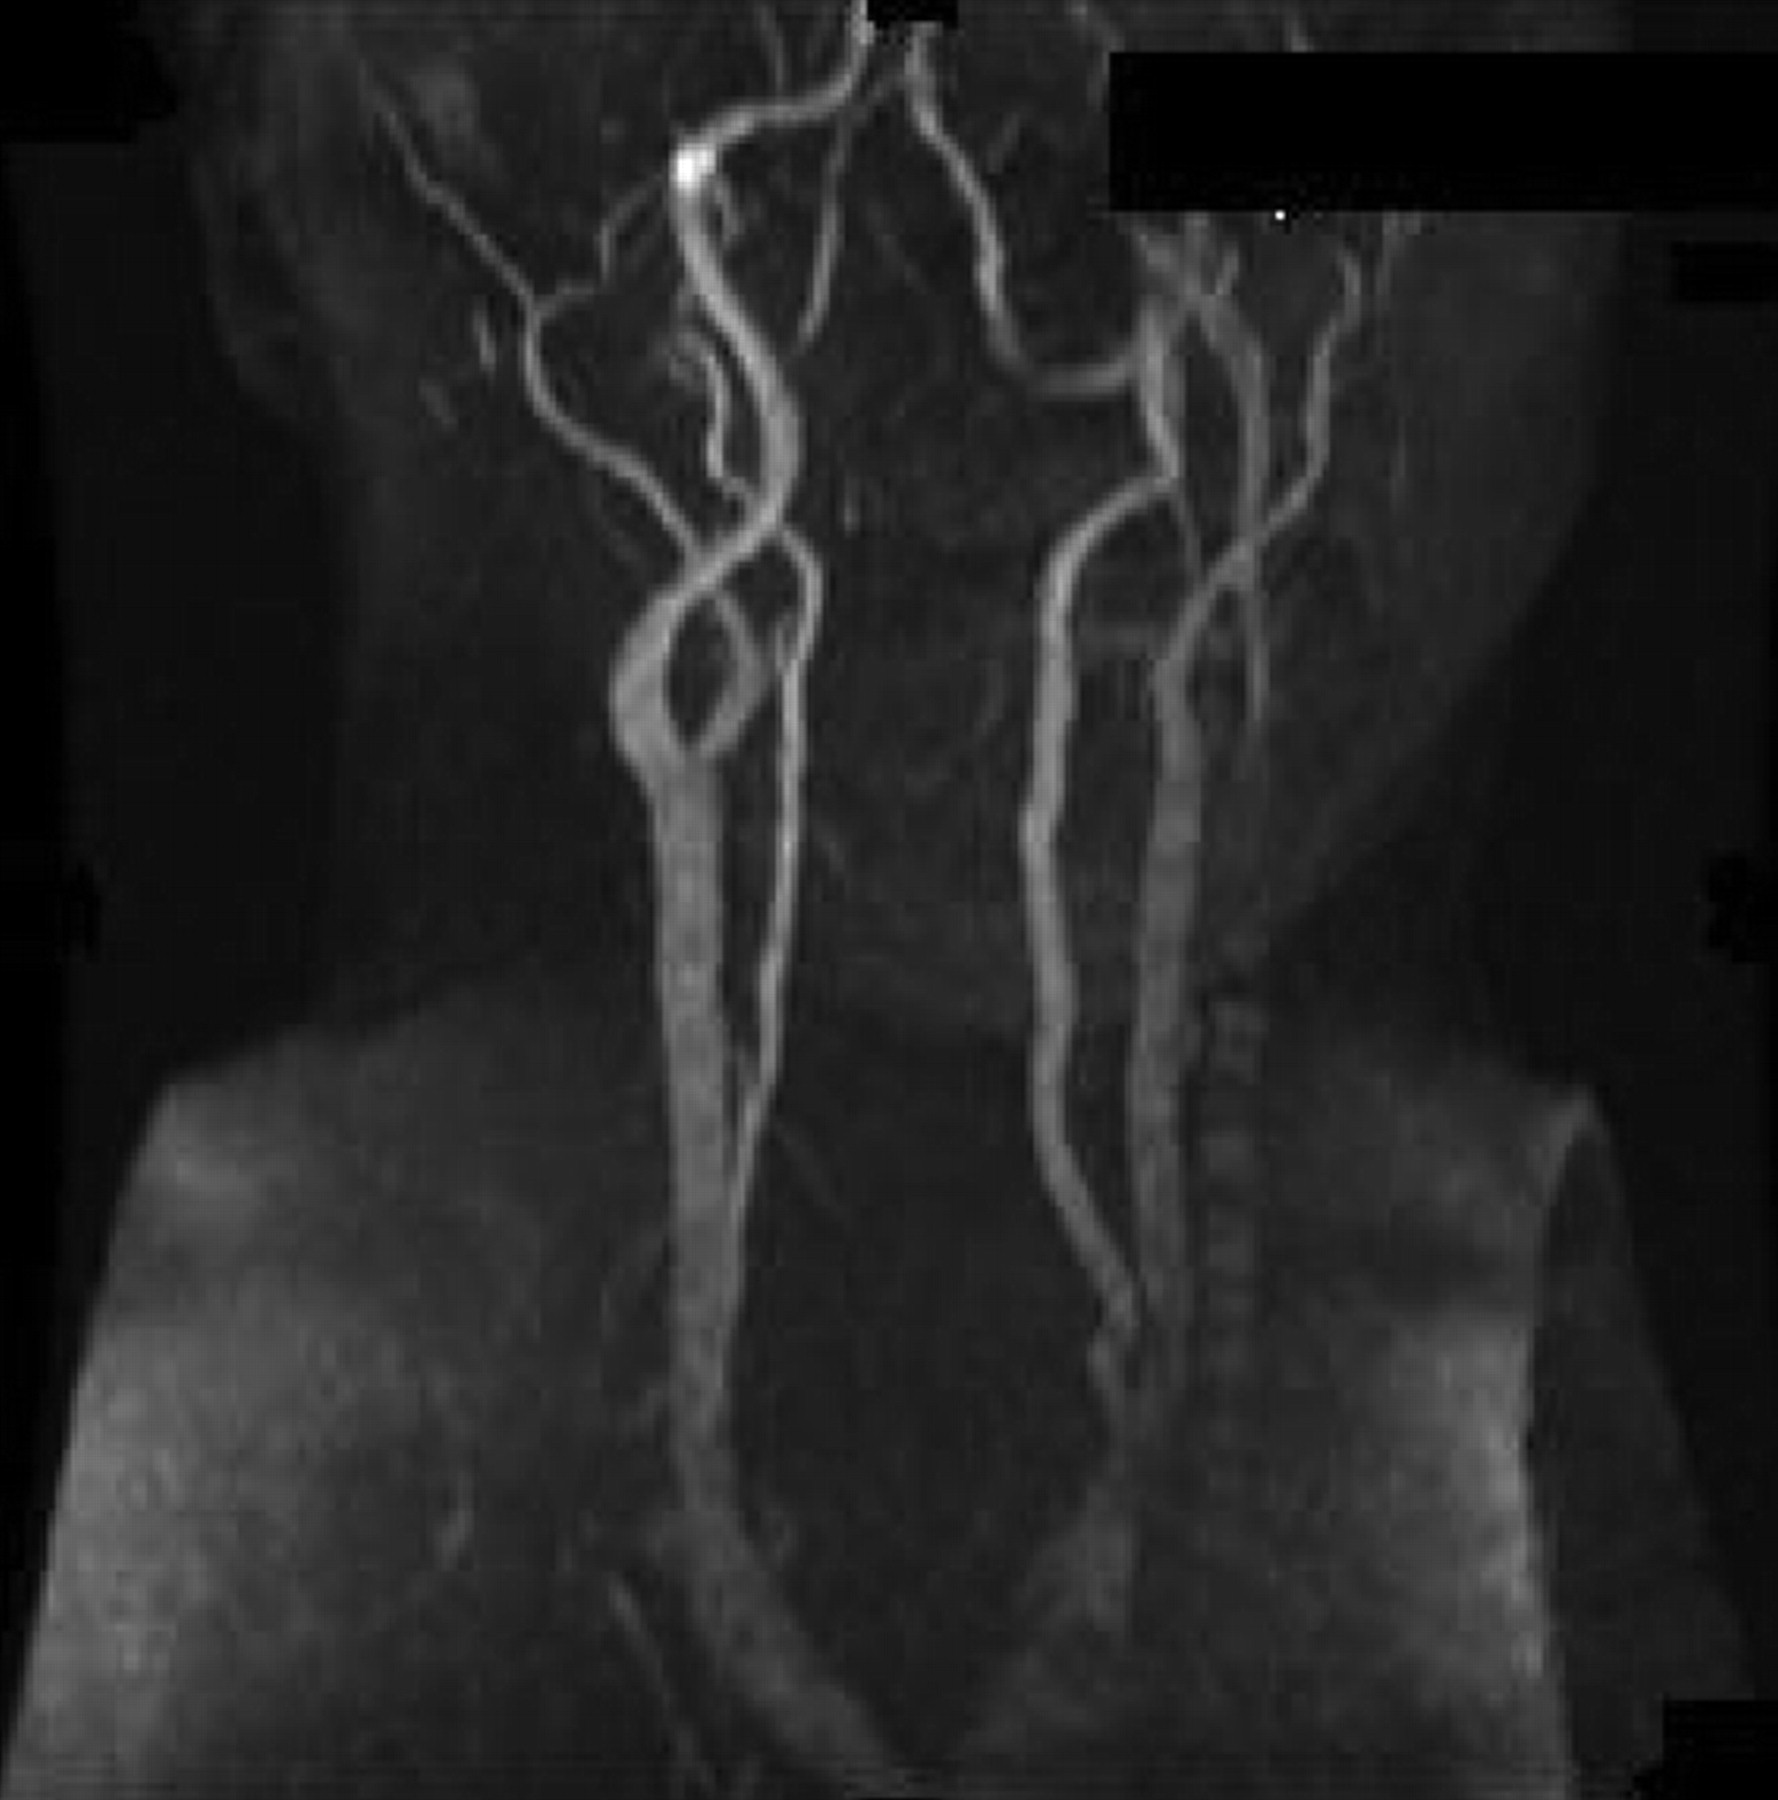

平均42岁男子,他的血压230/130毫米汞柱,面对权利brachiofacial弱点从急性左内部梗死。眼底镜检查显示严重高血压变化,盘水肿、动静脉尖酸刻薄的,和银布线,局限于右眼(图1)。视力是正常的。没有霍纳氏综合征或颈部疼痛。脖子先生扫描显示左颈内动脉严重狭窄,从起源到颅底,提示颈动脉解剖(图2)。结果血流量减少左视网膜免受严重高血压的影响。1加速高血压颈动脉解剖的可能的原因。2